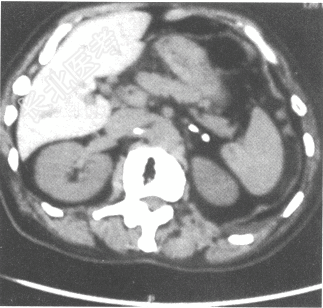

肾上腺CT:双侧肾上腺可见点状钙化,见下图。促肾上腺皮质激素238.06pg/ml(参考值7.2~63.3pg/ml)。最可能的诊断是什么